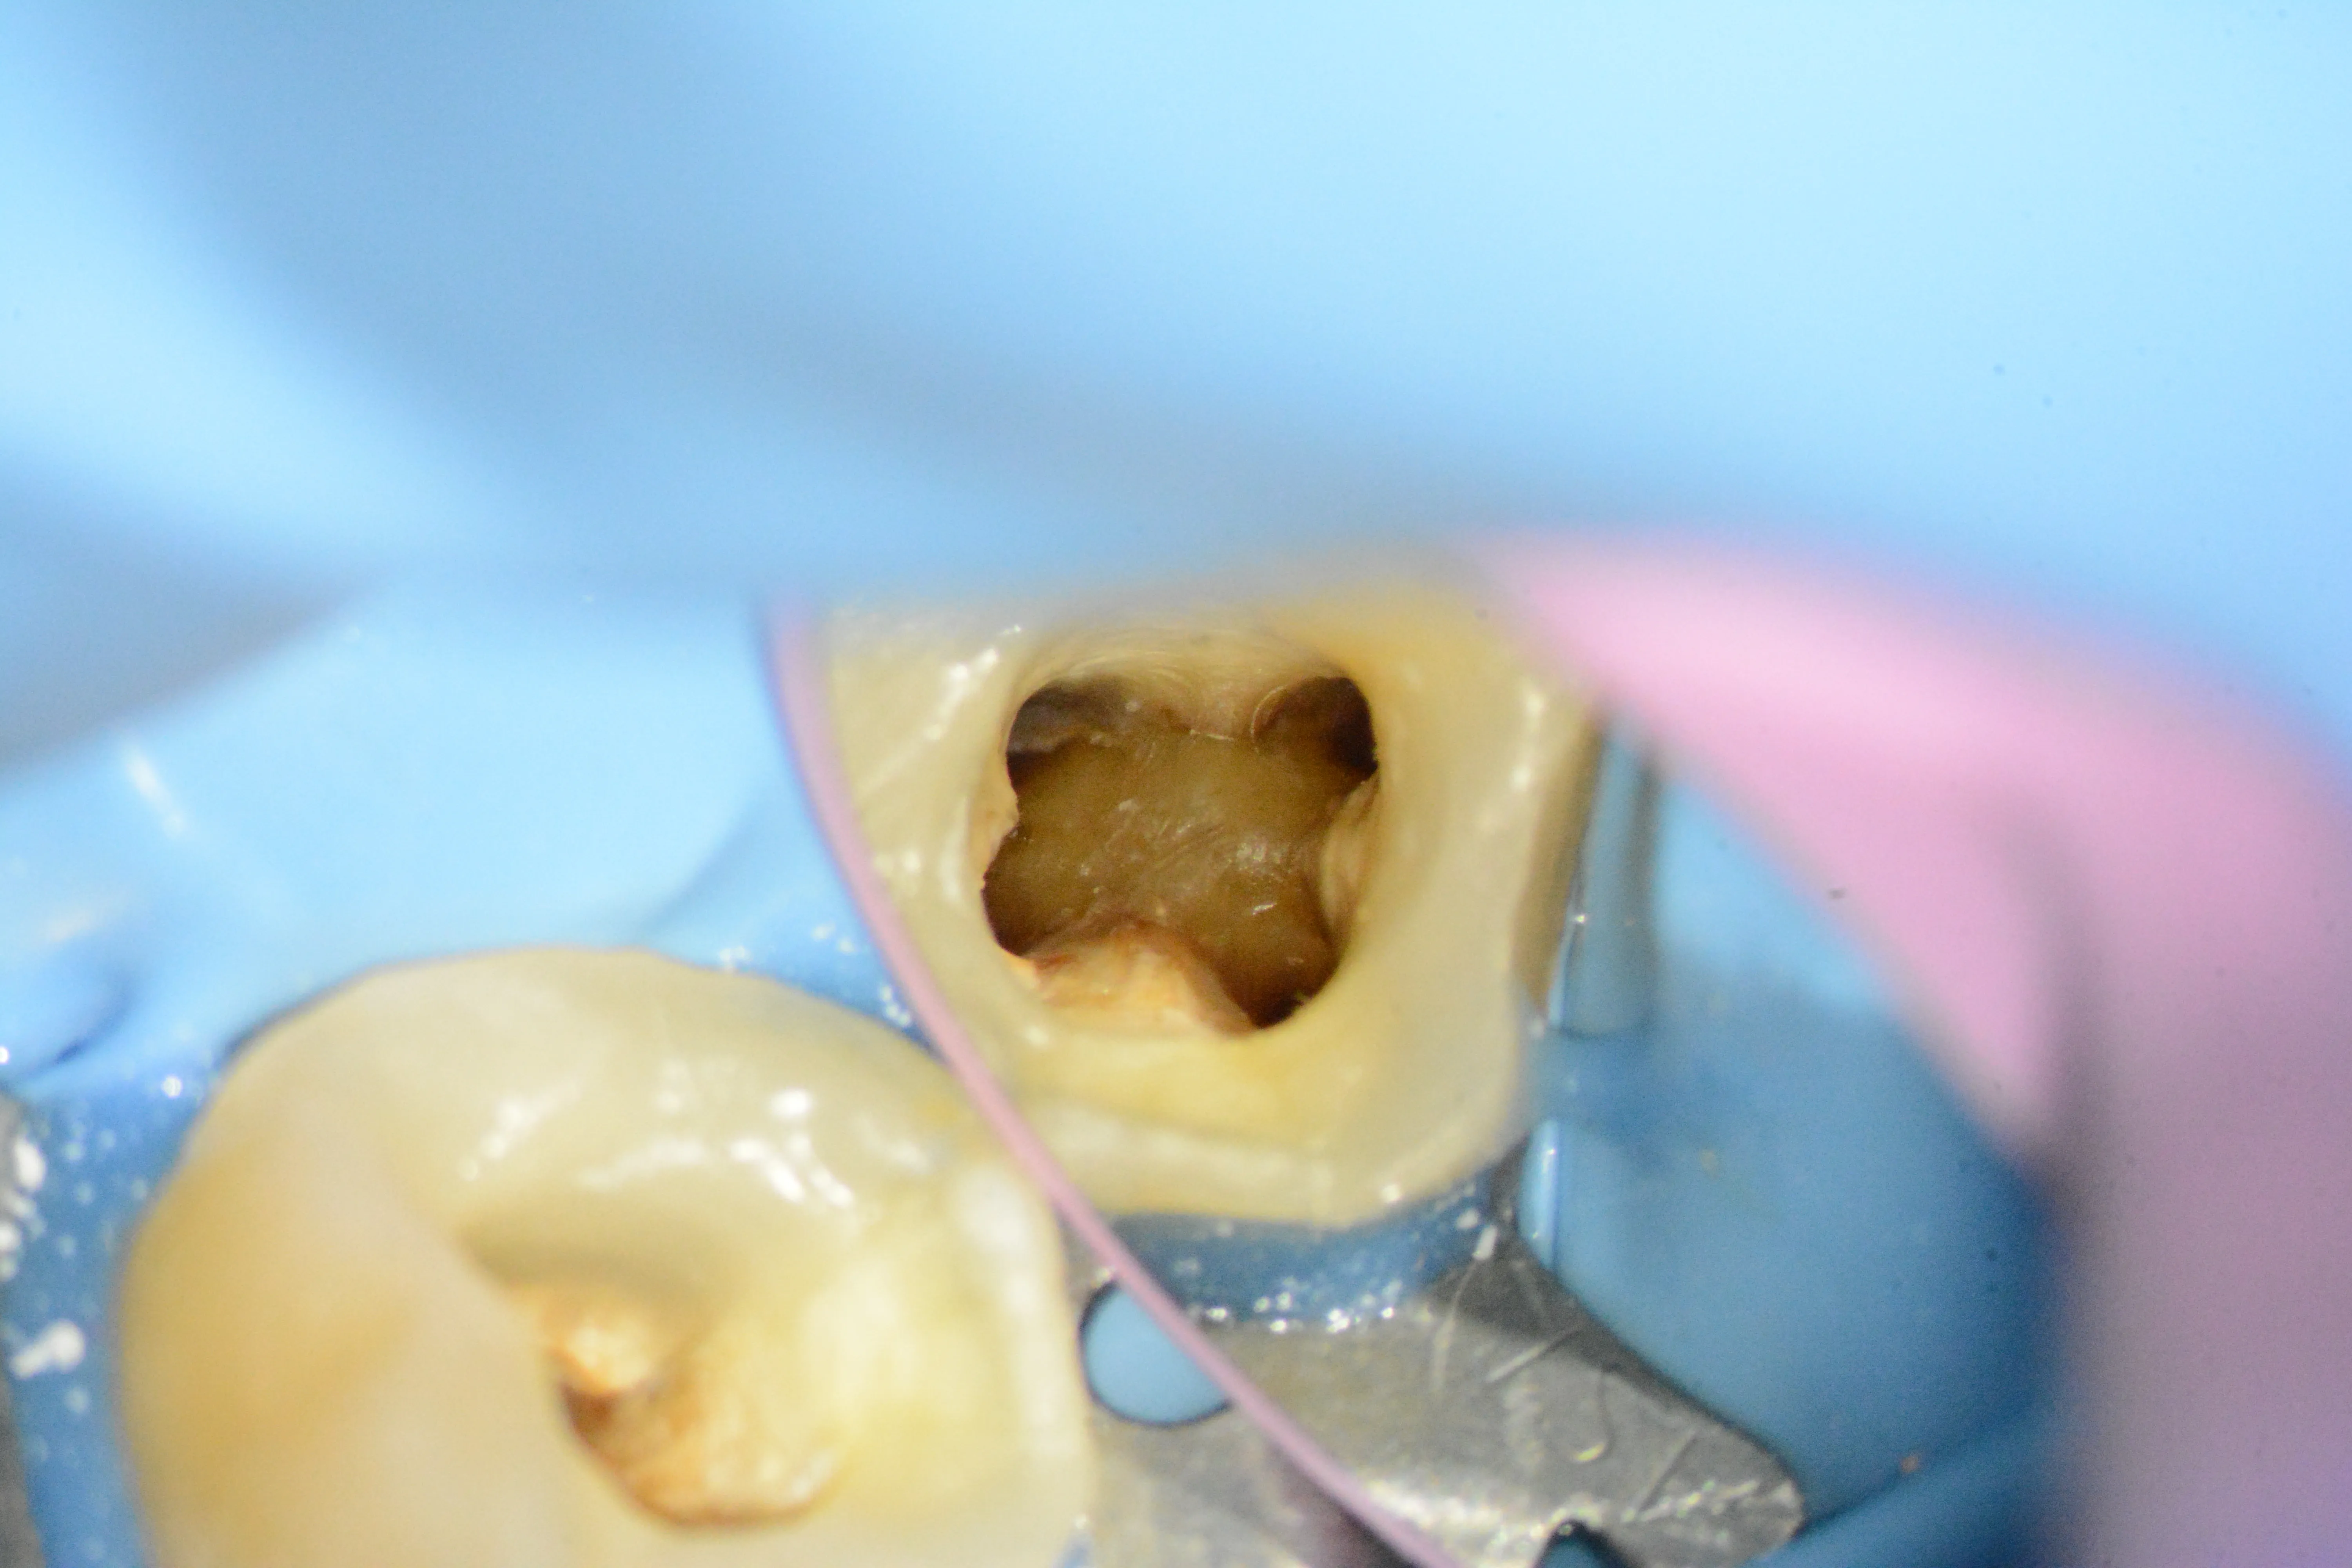

2 – Situația clinică inițială după îndepărtarea parțială a obturației coronare